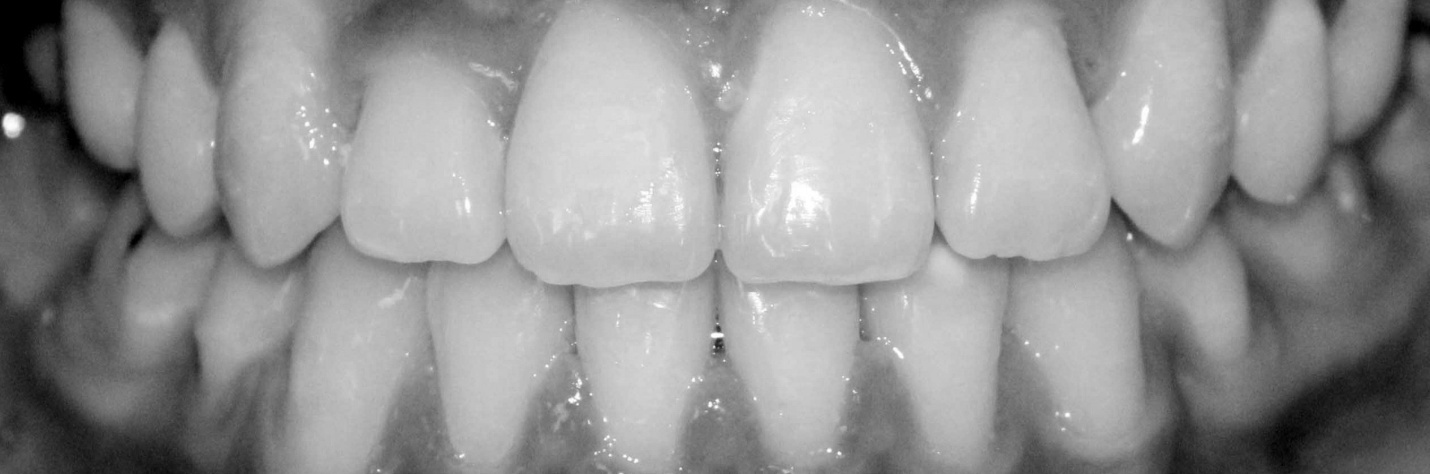

![]() |

| Bệnh nhân trước (ảnh trên) và sau khi được niềng răng. |